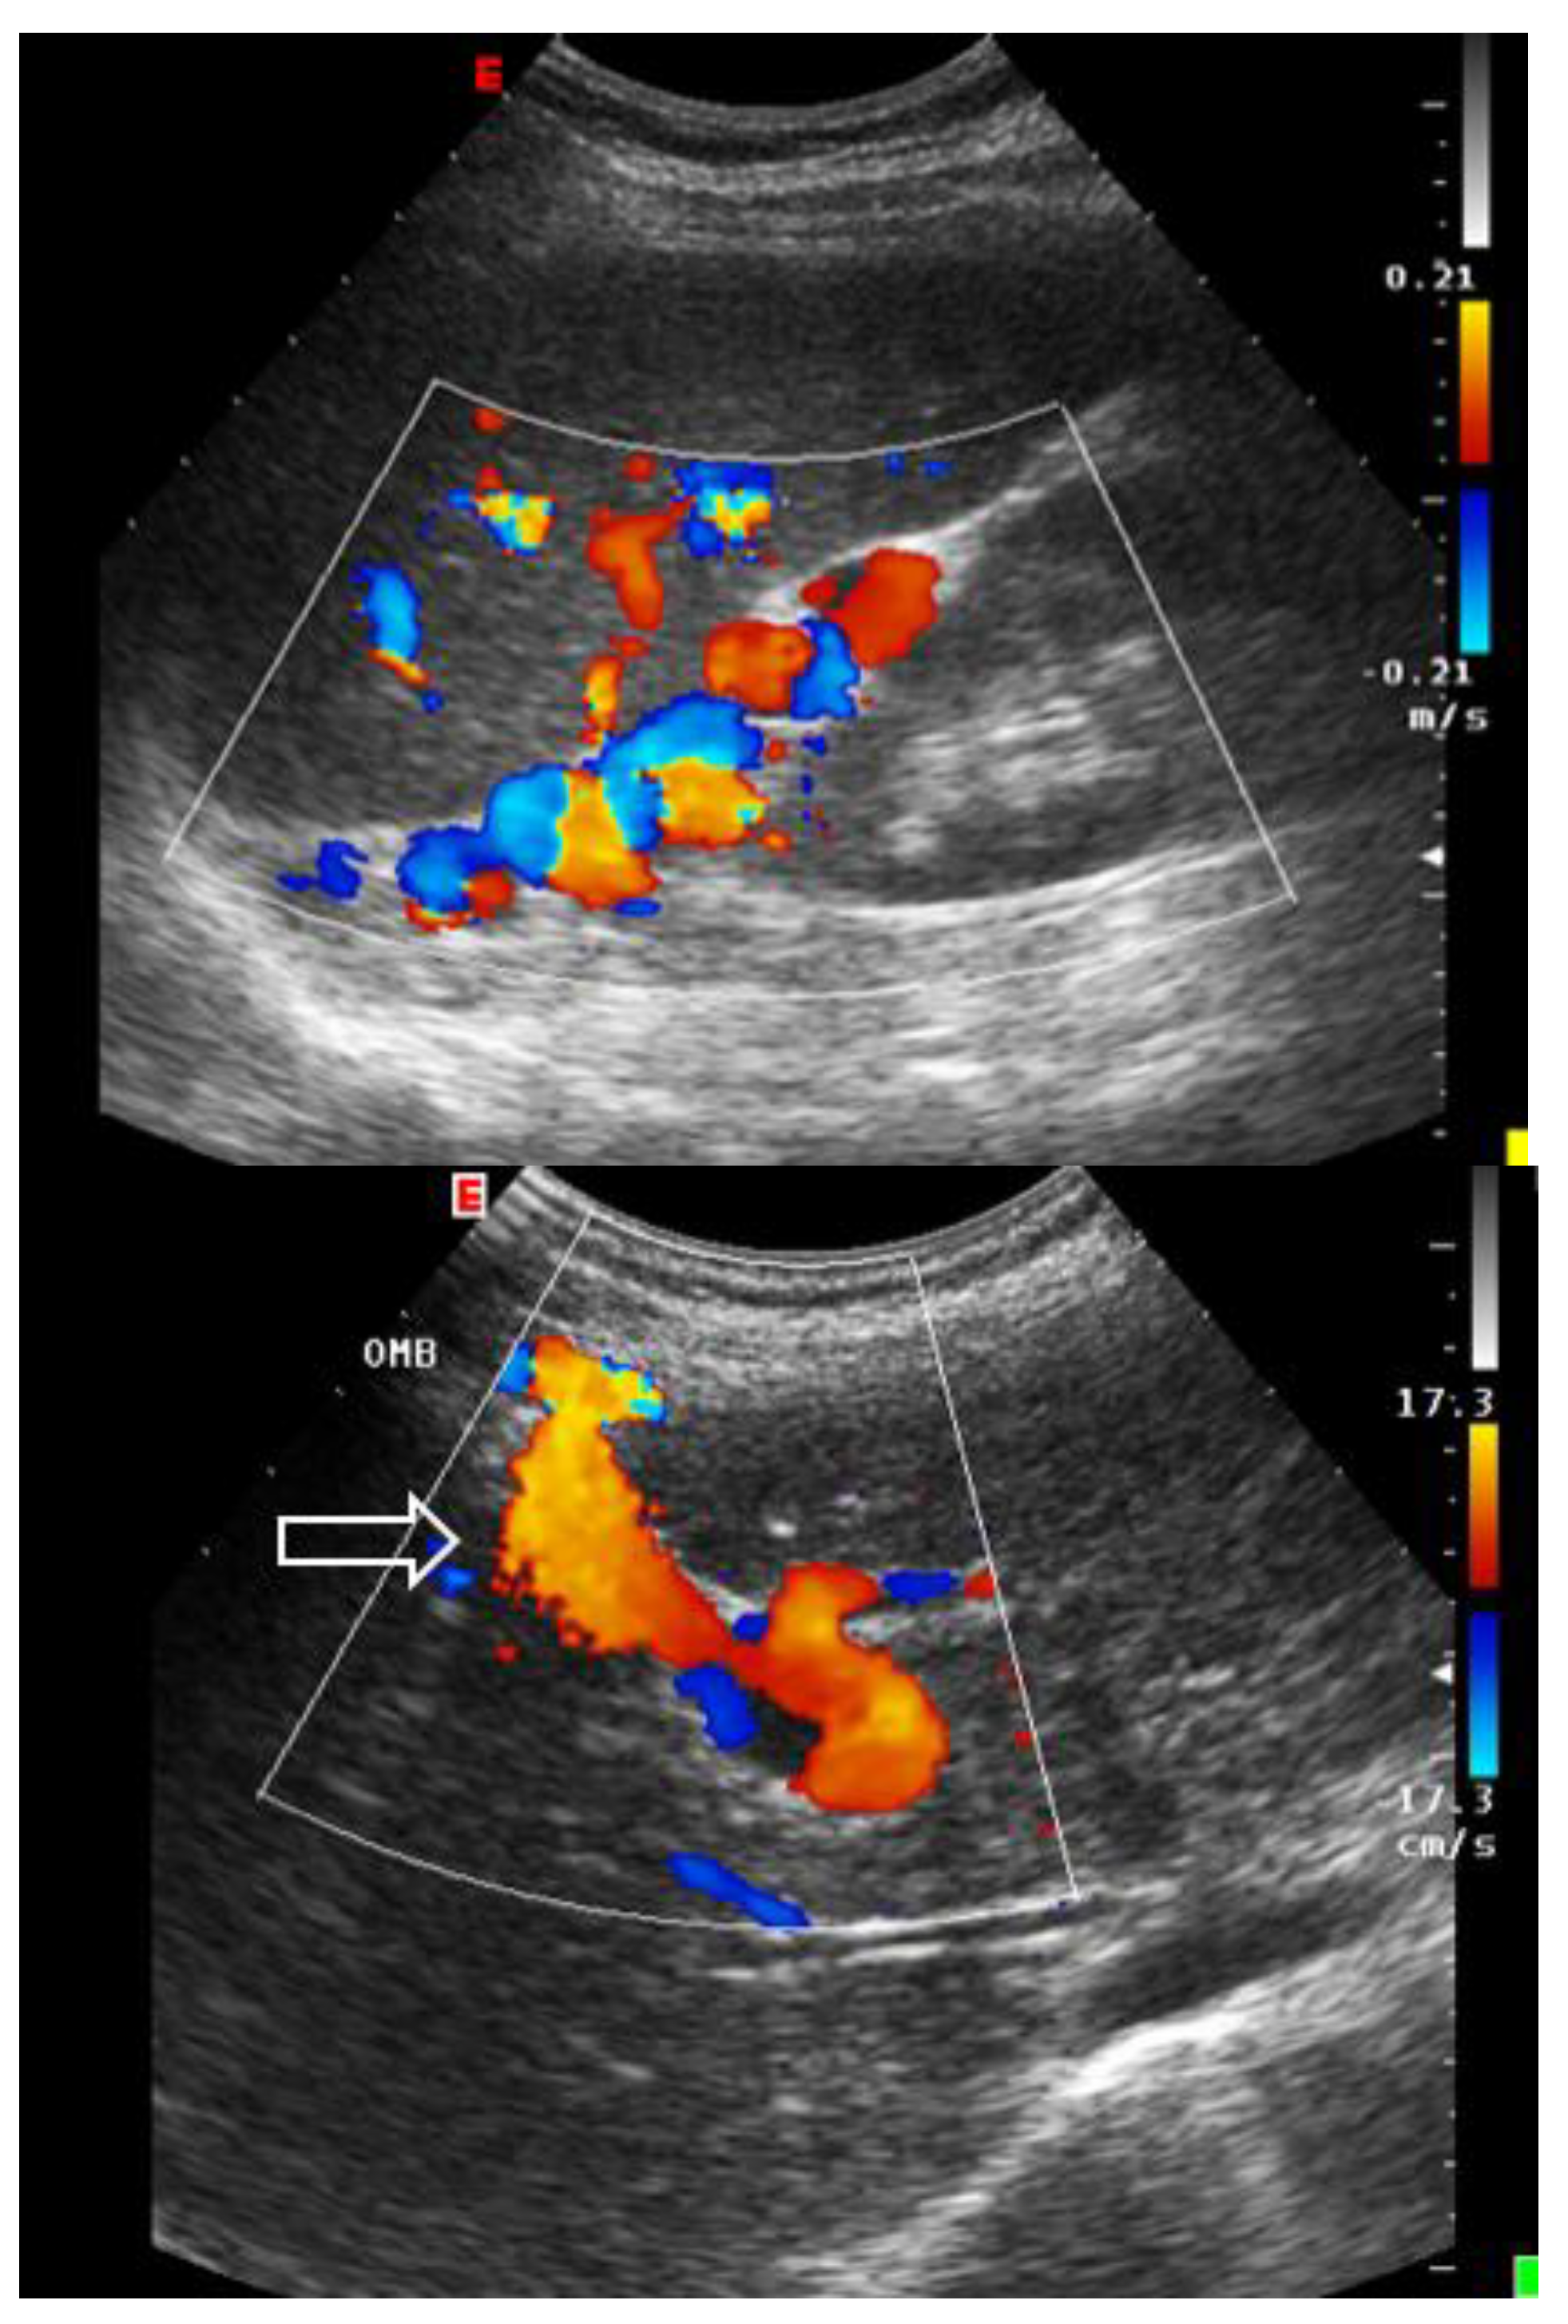

3.1.2. Ecocolordoppler and Spectral Velocity Variations:

PORTAL VEIN:

4. Absent (Aphasic) Portal Venous Flow:

- Hosoki, T.; Arisawa, J.; Marukawa, T.; Tokunaga, K.; Kuroda, C.; Kozuka, T.; Nakano, S. Portal blood flow in congestive heart failure: pulsed duplex sonographic findings. Radiology 1990, 174, 733-736. [CrossRef]

- Abu-Yousef, M.M.; Milam, S.G.; Farner, R.M. Pulsatile portal vein flow: a sign of tricuspid regurgitation on duplex Doppler sonography. AJR Am J Roentgenol 1990, 155, 785-788. [CrossRef]

- Gallix, B.P.; Taourel, P.; Dauzat, M.; Bruel, J.M.; Lafortune, M. Flow pulsatility in the portal venous system: a study of Doppler sonography in healthy adults. AJR Am J Roentgenol 1997, 169, 141-144. [CrossRef]

- Rengo, C.; Brevetti, G.; Sorrentino, G.; D'Amato, T.; Imparato, M.; Vitale, D.F.; Acanfora, D.; Rengo, F. Portal vein pulsatility ratio provides a measure of right heart function in chronic heart failure. Ultrasound Med Biol 1998, 24, 327-332. [CrossRef]

- Goncalvesova, E.; Lesny, P.; Luknar, M.; Solik, P.; Varga, I. Changes of portal flow in heart failure patients with liver congestion. Bratislavske lekarske listy 2010, 111, 635-639.

- Catalano, D.; Caruso, G.; DiFazzio, S.; Carpinteri, G.; Scalisi, N.; Trovato, G.M. Portal vein pulsatility ratio and heart failure. J Clin Ultrasound 1998, 26, 27-31. [CrossRef]

- Deschamps, J.; Denault, A.; Galarza, L.; Rola, P.; Ledoux-Hutchinson, L.; Huard, K.; Gebhard, C.E.; Calderone, A.; Canty, D.; Beaubien-Souligny, W. Venous Doppler to Assess Congestion: A Comprehensive Review of Current Evidence and Nomenclature. Ultrasound Med Biol 2023, 49, 3-17. [CrossRef]

- Bouabdallaoui, N.; Beaubien-Souligny, W.; Oussaid, E.; Henri, C.; Racine, N.; Denault, A.Y.; Rouleau, J.L. Assessing Splanchnic Compartment Using Portal Venous Doppler and Impact of Adding It to the EVEREST Score for Risk Assessment in Heart Failure. CJC Open 2020, 2, 311-320. [CrossRef]